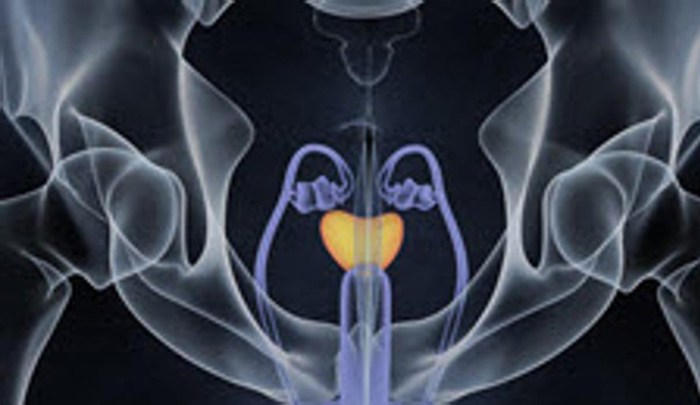

El 90 por ciento de los pacientes con cáncer de próstata se pueden curar si son diagnosticados precozmente, según ha comentado el jefe de servicio de Urología del Instituto de Cirugía Urológica Avanzada (ICUA)-Clínica Centro, Fernando Gómez Sancha, con motivo del Día Mundial de la enfermedad que se celebra este jueves. "Con un diagnóstico precoz, … Continuar leyendo El 90% de los pacientes con cáncer de próstata se pueden curar si son diagnosticados precozmente

Cáncer de próstata, una enfermedad silenciosa que se puede prevenir

El 11 de junio de cada año se conmemora el Día Mundial del Cáncer de Próstata como una oportunidad para sensibilizar a la sociedad sobre esta enfermedad e informar de la importancia del diagnóstico precoz y de los recursos y posibilidades para su tratamiento. “El gran ‘Cuco’ de los hombres es el cáncer de próstata”, sostuvo el … Continuar leyendo Cáncer de próstata, una enfermedad silenciosa que se puede prevenir